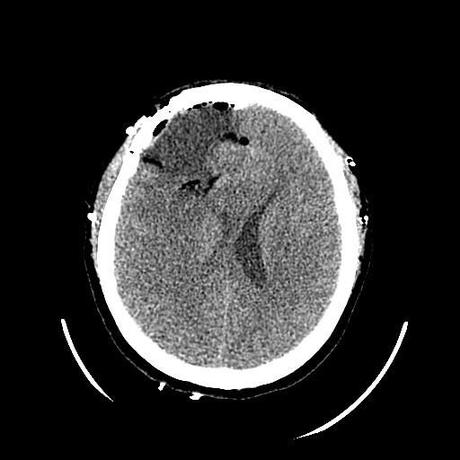

Corte axial post quirúrgico, adecuada resección de lesión. Axial CT scan, showing a proper tumor resection

Corte axial post quirúrgico, adecuada resección de lesión.

El reporte fue glioma de alto grado (GB), posteriormente la paciente acudirá para manejo adyuvante con quimio y radioterapia